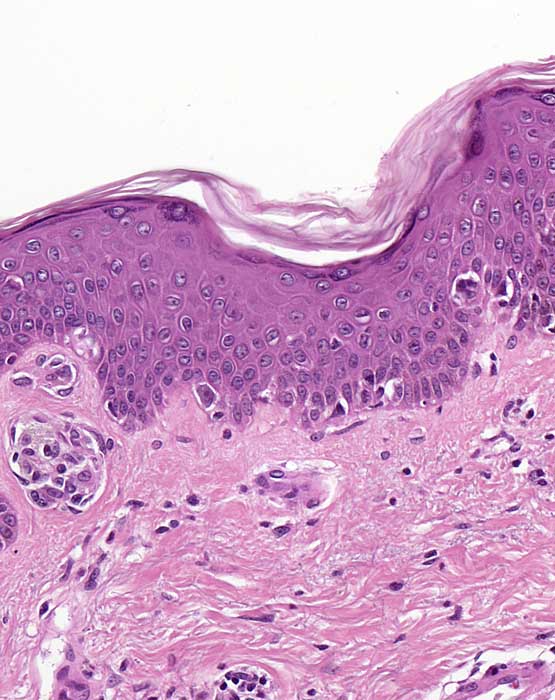

PathoPic ID 6725 - naevoides Melanom: unscharfe laterale Begrenzung

naevoides Melanom: unscharfe laterale Begrenzung

maligner Tumor

Haut, Rumpf

Haut

Die laterale Begrenzung des Melanoms ist unscharf. Die laterale Begrenzung wird gebildet durch

atypische Einzelzellen und

kleine Nester in unregelmässigen Abständen.

Histologie

200